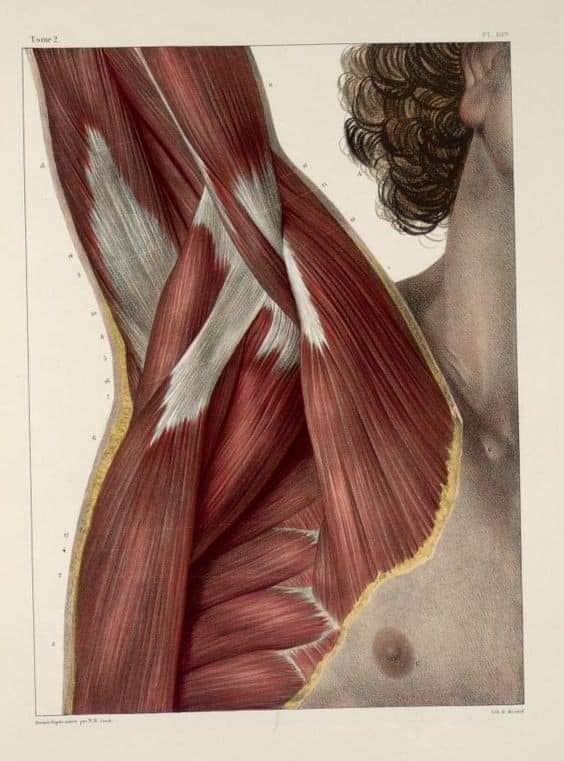

Поверхневі спинні м'язи

М'язи, що піднімають лопатку: Трапецієподібний м'яз: великий м'яз, що покриває верхню частину спини. Його функція - підтримка і рух лопаток, а також забезпечення стабільності хребта.

М'язи, що ведуть лопатку до хребта: Широкий м'яз спини: великий м'яз, що розташований в нижній частині спини. Він відповідає за рухи плечей і лопаток, а також за розширення верхньої частини тулуба.